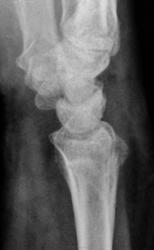

Боли. Травма в анамнезе была, но за помощью не обращался.

Похоже вколоченный перелом диафиза лучевой кости.

Перелом метаэпифиза луча

консолидированный вколоченный перелом метаэпифиза лучевой кости